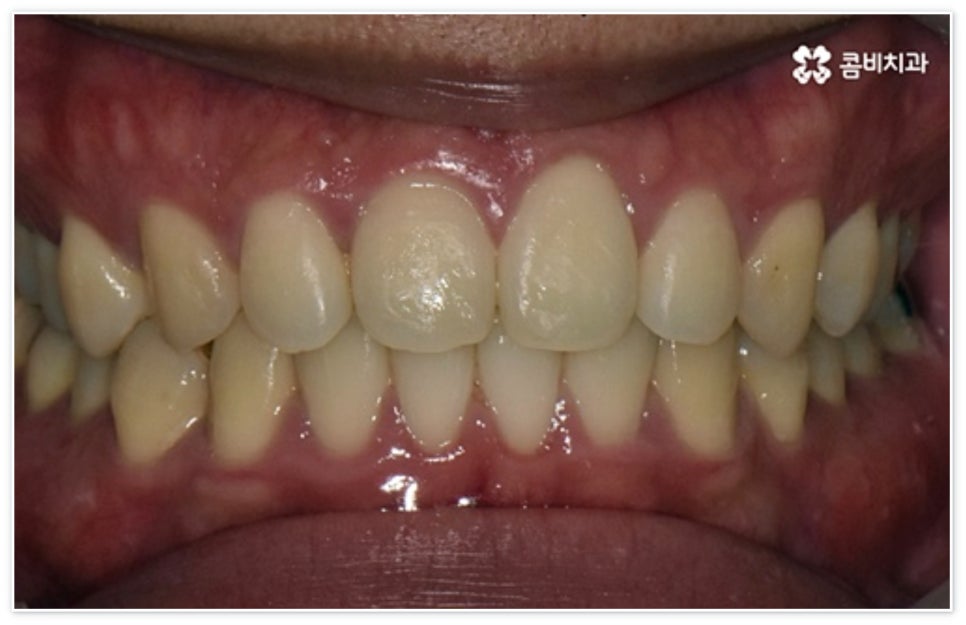

환자분들에 따라 다르지만 통상적으로 전체 교정이 1년에서 2년 반 정도 소요된다면 부분 교정은 6~8개월 정도로 기간 단축이 가능하여 치료에 대한 부담을 줄일 수 있으며 대부분 발치 과정 없이 필요한 부위에만 브라켓을 부착하는 만큼 불편함이 적고 구강 관리도 용이한 편이니 (사진에서 살펴볼 수 있는 케이스) 이에 대해서 자세히 알아보시면 좋을 거예요. 물론 누구나 가능한 것은 아니고 개인의 구강 상태에 따라 진행을 해야 하므로 꼼꼼한 검진과 충분한 상담부터 받아보시길 권유드리고 있습니다.